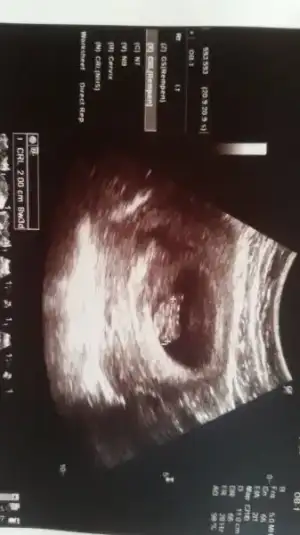

• IMG-20160502-WA0006.webp

IMG-20160502-WA0006.webp

11,5 KB · Görüntüleme: 83

Sa benim yapılan tahmin turmustuBuda arkadaşımın görüntüsü yorum yağabilirseniz cok sevinirim .şimdiden cok tşk ederim